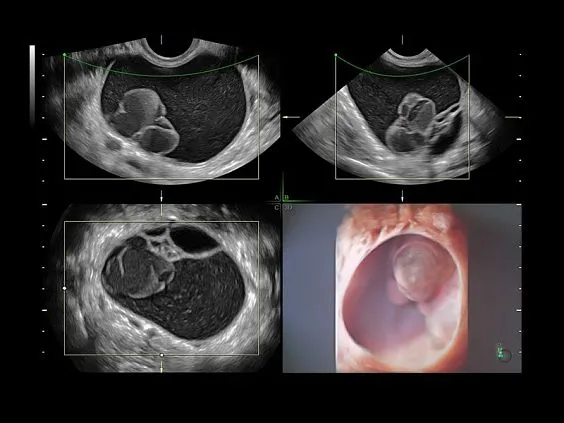

Клинические изображения

- Томографический ультразвук (TUI).

- Объемное контрастирование прямой плоскости — Basic VCI (VCI-A + VCI Static).

- Advanced STIC — расширенный программный пакет для исследования сердца плода в режиме 4D для объемных датчиков:

- SonoVCADHeart — программное обеспечение для исследования сердца плода в режиме 3D/4D (быстрый доступ к плоскостям сканирования) по рекомендациям ISUOG.